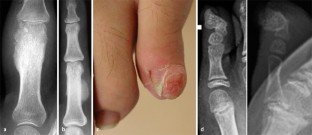

Abb. 3